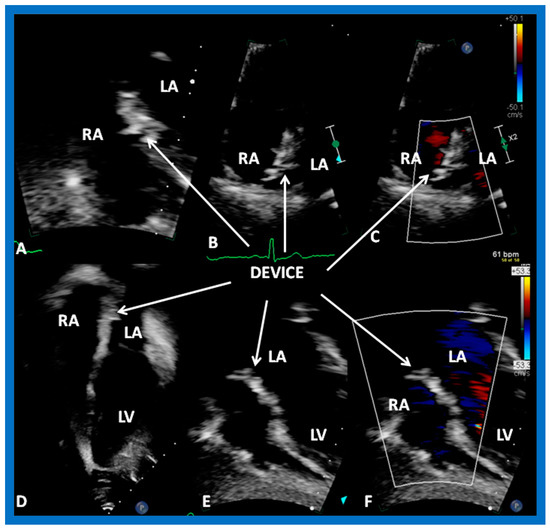

8. Device Occlusion

9.2. Device Position